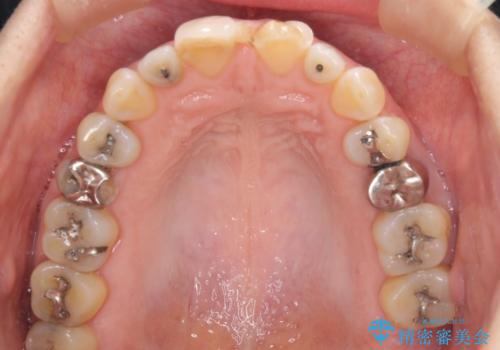

- 前歯のすきっぱを主訴にご来院された患者様です。他院でつめものやラミネートべニア(前歯の表面のみセラミックを貼り付ける)を行っていましたが、頻繁に外れることに悩まれており、クラウン(歯全体をセラミックがつつむ)をご希望されました。また、奥歯に大きな虫歯があり、歯が割れていたため、奥歯の治療も併せて行いました。

今回はまず欠けた場所を修復して見た目を回復させたのち、ラミネートべニアの仮歯をつくり、しばらく使用して考えて頂きました。メリットやデメリットを説明した結果、外れにくいセラミッククラウンをご選択頂きました。

咬み合わせや元のご自身の歯の色に特徴があったため、セラミッククラウンを修正したり、隣の歯を金属を外して白いつめものに変えたりして経過観察を長めに行いました。

右上の歯に関しても、大きな虫歯があったため、前歯の経過観察の間に治療を行いました。